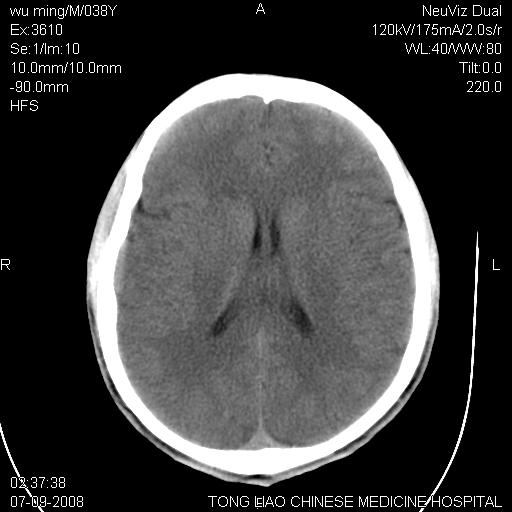

考虑:面骨、颅底骨多发骨折,颅内高压(脑肿胀)。

面骨、颅底骨多发骨折,右侧硬膜下小血肿,弥漫轴索损伤,死亡原因可能是多种因素致。

不除外轴索损伤

颅底骨折,窦腔内积血。考虑死亡原因为脑水肿压迫脑干或因大量失血死亡。

考虑:面骨、颅底骨多发骨折。从五楼摔下还伤着头了,不死才怪;估计有弥漫性轴索损伤。